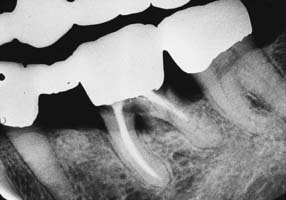

Detecting disease around an FDP can be extremely difficult at a stage when corrective treatment is still relatively simple. For instance, partial dissolution of the luting agent may be difficult to diagnose with a subgingival margin. Caries is often detected only after irreversible pulp involvement has resulted. Caries under a crown is more difficult to detect radiographically, although bitewing images provide some information interproximally. Follow-up studies on patients with FDPs reveal that identifying risk factors and predicting the development of caries in any particular patient are complicated. However, there is no indication that caries is more likely in association with prostheses than on unrestored teeth.3

Radiolucent cements should be avoided because detecting excess luting agent radiographically is impossible if that material is effectively radiolucent. As luting agent radiopacity increases, excess cement is spotted more easily on routine radiographs; therefore, the dentist should choose a luting agent that is as radiopaque as possible. In practice, luting agents are available in a wide range of radiopacities.4-6 Figure 32-5 summarizes data from these studies.

Fig. 32-5 Radiopacity of luting agents. In three in vitro studies,4-6 investigators compared the radiographic appearance of various luting agents to aluminum. The data were normalized to account for different specimen thicknesses used by the investigators. Excess luting agent is more difficult to detect if materials with lower values are chosen. In addition, margin gaps and recurrent caries are more difficult to diagnose.